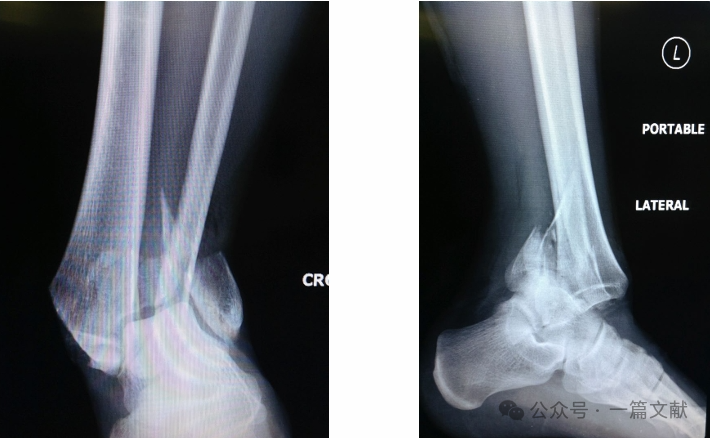

联合拉力螺钉及关节骨块钢板固定时,可为粉碎性骨折区域提供早期稳定性以促进愈合。如下图: